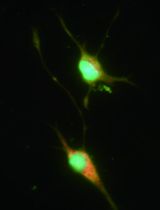

Clearance of dead brain tissue including the dead neurons through phagocytosis is an endogenous function of microglia in the brain, which is critical for inflammation resolution after ischemic stroke or head trauma. By regulating the function or polarization status of microglia, we may control their phagocytosis efficacy and therefore the cleanup process for the dead brain tissue. We cultured rat cortical neurons and microglia from the same litter of embryos. The cultured neurons are subjected to irradiation for inducing neuronal apoptosis. After labeling with propidium iodide (PI), the dead neurons (DNs) are exposed to the cultured microglia for phagocytosis assay. By counting the number of DNs in each microglia, we calculate the phagocytosis index to quantify the phagocytosis efficacy of microglia toward DNs. The protocol is divided into 4 sections: A) culturing rat cortical neurons from pre-natal rat embryos, B) preparing dead neurons as phagocytosis target, C) culturing rat brain microglia, D) quantifying phagocytosis index of microglia toward the dead neurons.